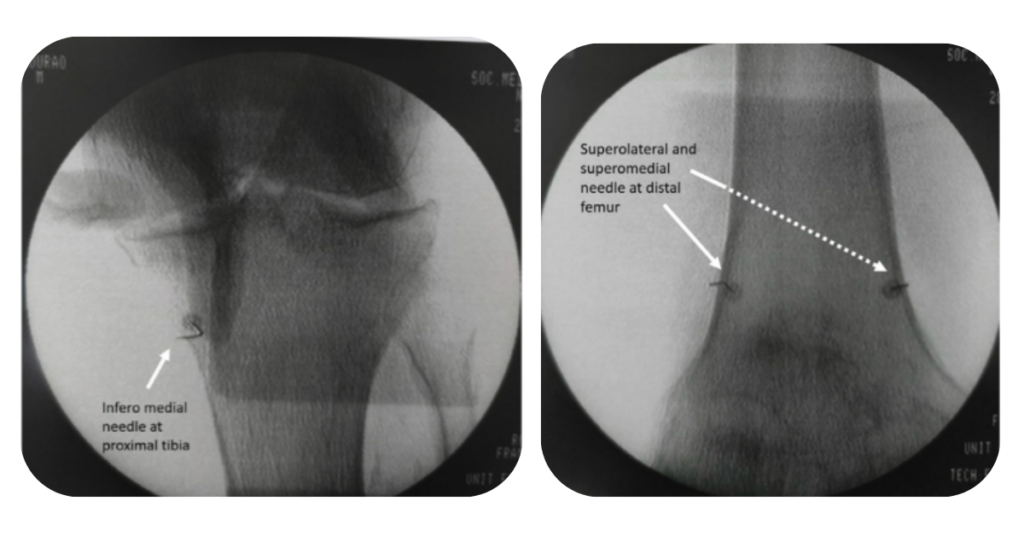

A rizotomia por radiofrequência é indicada para pacientes com dor crônica no joelho, especialmente com artrose avançada, que não querem ou não podem realizar cirurgia. O procedimento consiste em:

• Inativar temporariamente os nervos geniculados (que transmitem a dor)

• Realizado com agulhas finas e tecnologia de radiofrequência

• Pode durar de 6 a 12 meses

É uma excelente opção para idosos com contraindicações cirúrgicas, ou como ponte até a colocação de uma prótese.